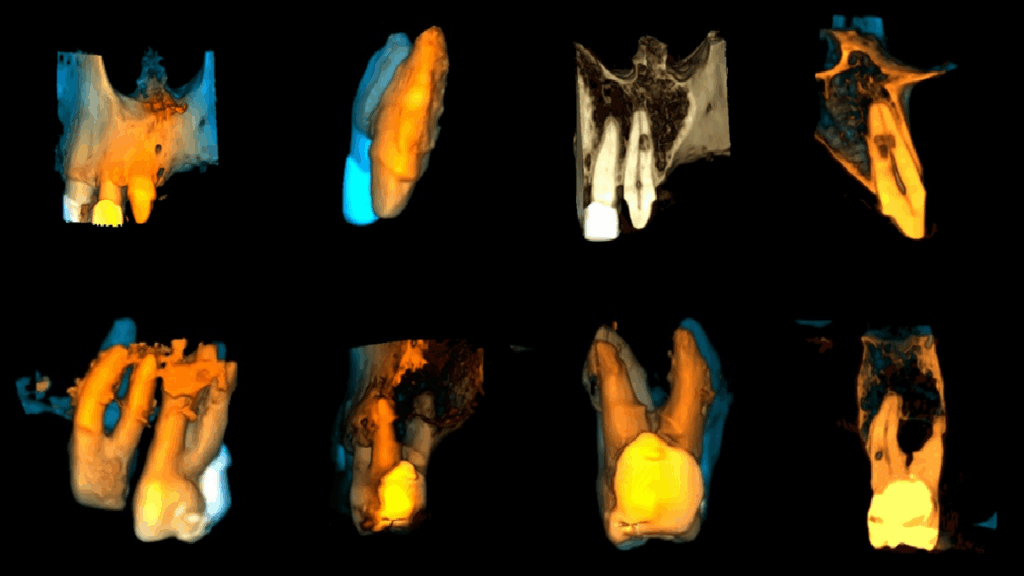

A la evaluación de la tomografía cone beam de campo mediano (FOV = 10 x 10) se observa en la pieza 11 la presencia de una imagen hipodensa de forma irregular localizada a niel de tercio medio radicular y que se compromete la dentina radicular por mesial y palatino, asimismo se observa la pieza 27 que además de la restauración presenta una imagen hipodensa en raíz palatina a nivel de tercio medio radicular y finalmente un trazo de fractura vertical por distal que compromete la zona de furcación y ocasiona un proceso osteolítico interradicular.

RECONSTRUCCIÓN 3D